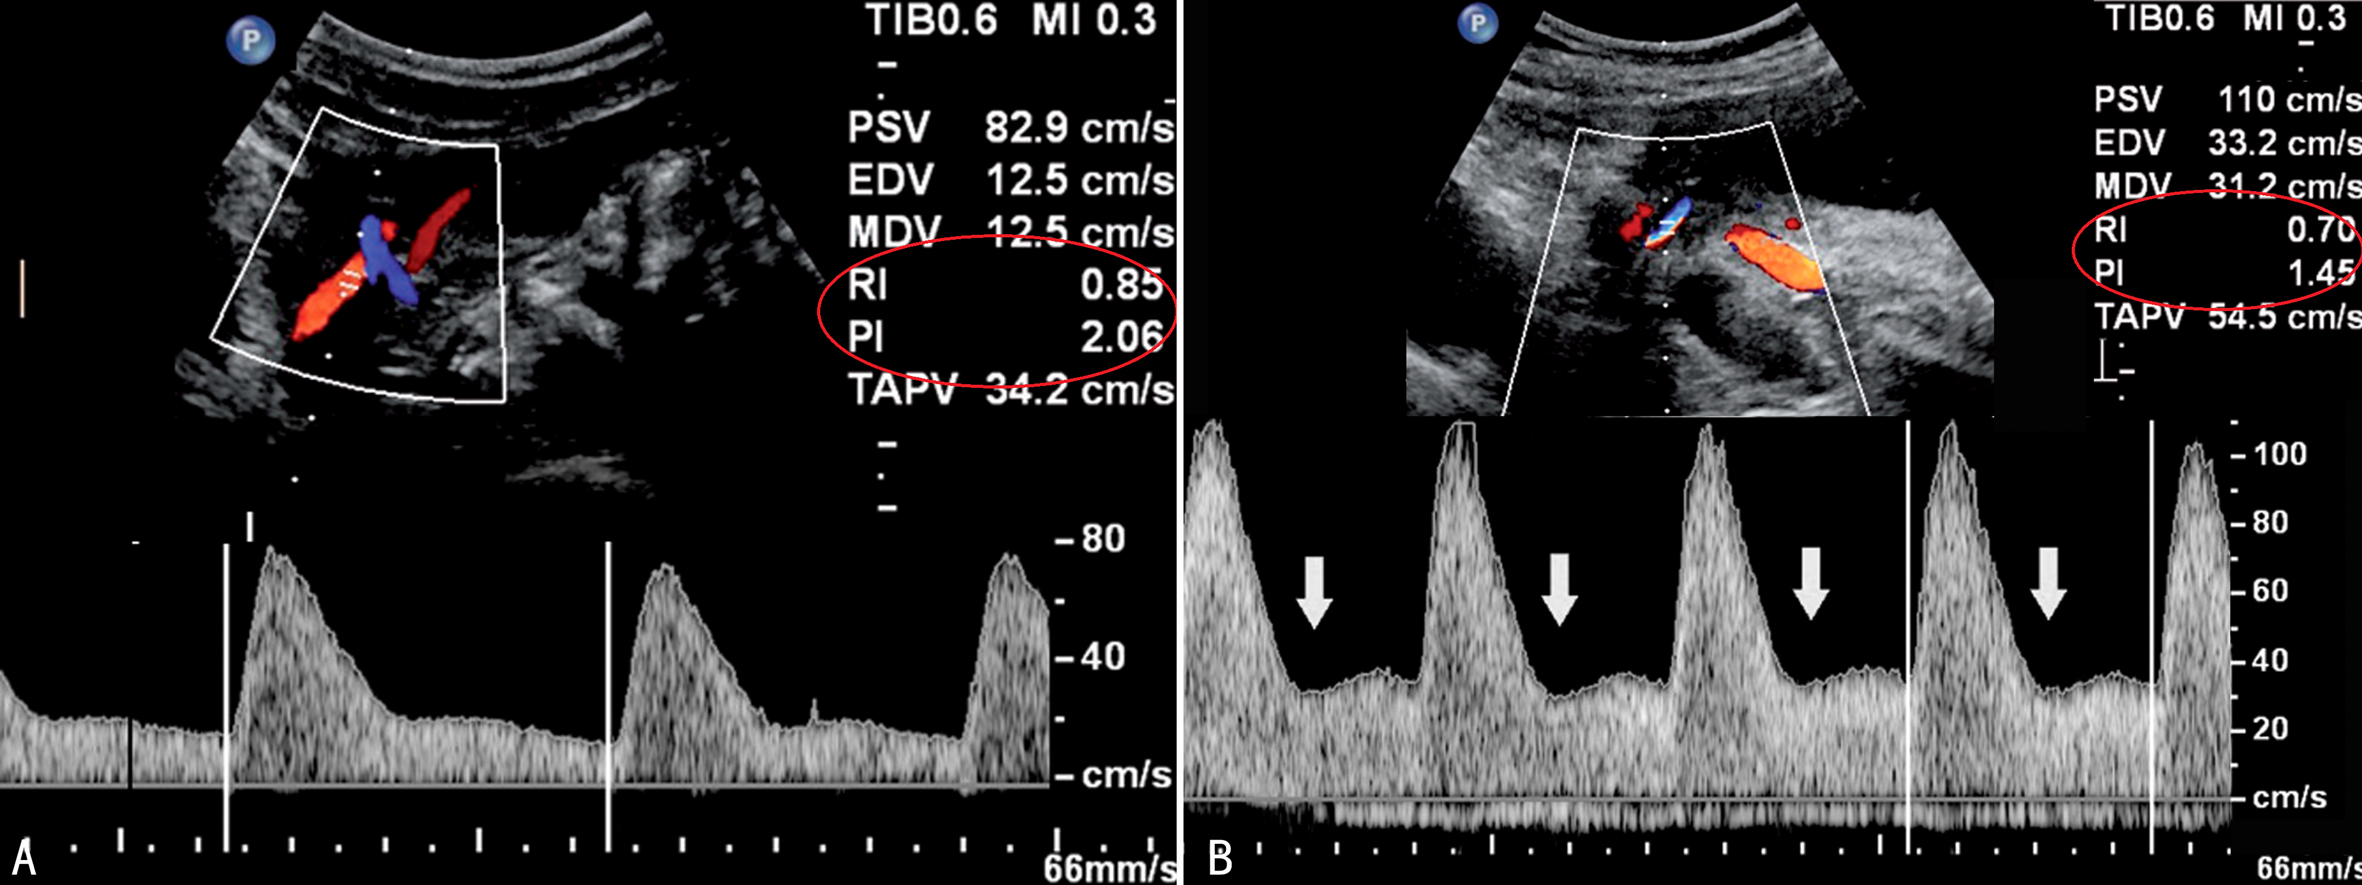

1.UA 研究证实UA的超声检查对子痫的发生有预测价值。随着孕周进展,正常妊娠组孕妇UA RI、PI和S/D均逐渐降低;妊娠期高血压疾病孕妇UA RI、PI逐渐升高,RI在妊娠中期达最高值,晚期略有下降;而RI和S/D在妊娠中、晚期均明显升高;与妊娠期高血压疾病孕妇比较,子痫前期孕妇UA平均血流阻力明显地高于正常妊娠。而这种变化在妊娠早期就已经显现,并且对子痫前期的预测价值高于对胎儿发育迟缓的预测价值,尤其是PI增加合并舒张早期PN(图1)更具有意义,并且可以伴有搏动性子宫静脉血流速度曲线(图2)。

图1 21周妊娠期子宫动脉血流速度曲线(A),左侧箭头示PN,但PI和RI并没有增加

图2 PN(A)与搏动性子宫静脉血流速度曲线(B)

2.子宫静脉(UV) 伴随UA血流的异常,UV血流也发生异常变化(图2B),出现明显的切迹(Ⅱ型)或舒张期血流消失(Ⅲ型)。